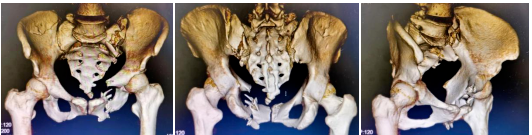

患者为60岁老年女性,因意外致胸部、骨盆处及双下肢疼痛,活动受限,急诊行X线检查示:多发性骨盆骨折、左侧骶髂关节脱位、右侧骼骨骨折、多处肋骨骨折、创伤性胸腔积液等,由创伤骨科收治入院。

术前

术中,先用骨盆牵引床,在C臂机监视下牵引左下肢,复位左侧骶骼关节后,骨科手术机器人通过专用C型臂透视下取得手术部位的图像,在电脑上分别规划好最佳置钉路径,机械臂随动运行调整到最佳角度,引导医生置入骶髂螺钉和INFIX螺钉,连接弯棒完成骨盆前环固定,透视各个角度见骨折复位及固定满意,无螺钉进入骶管及关节腔,切口予以全层缝合,手术顺利,术中出血仅20ml。